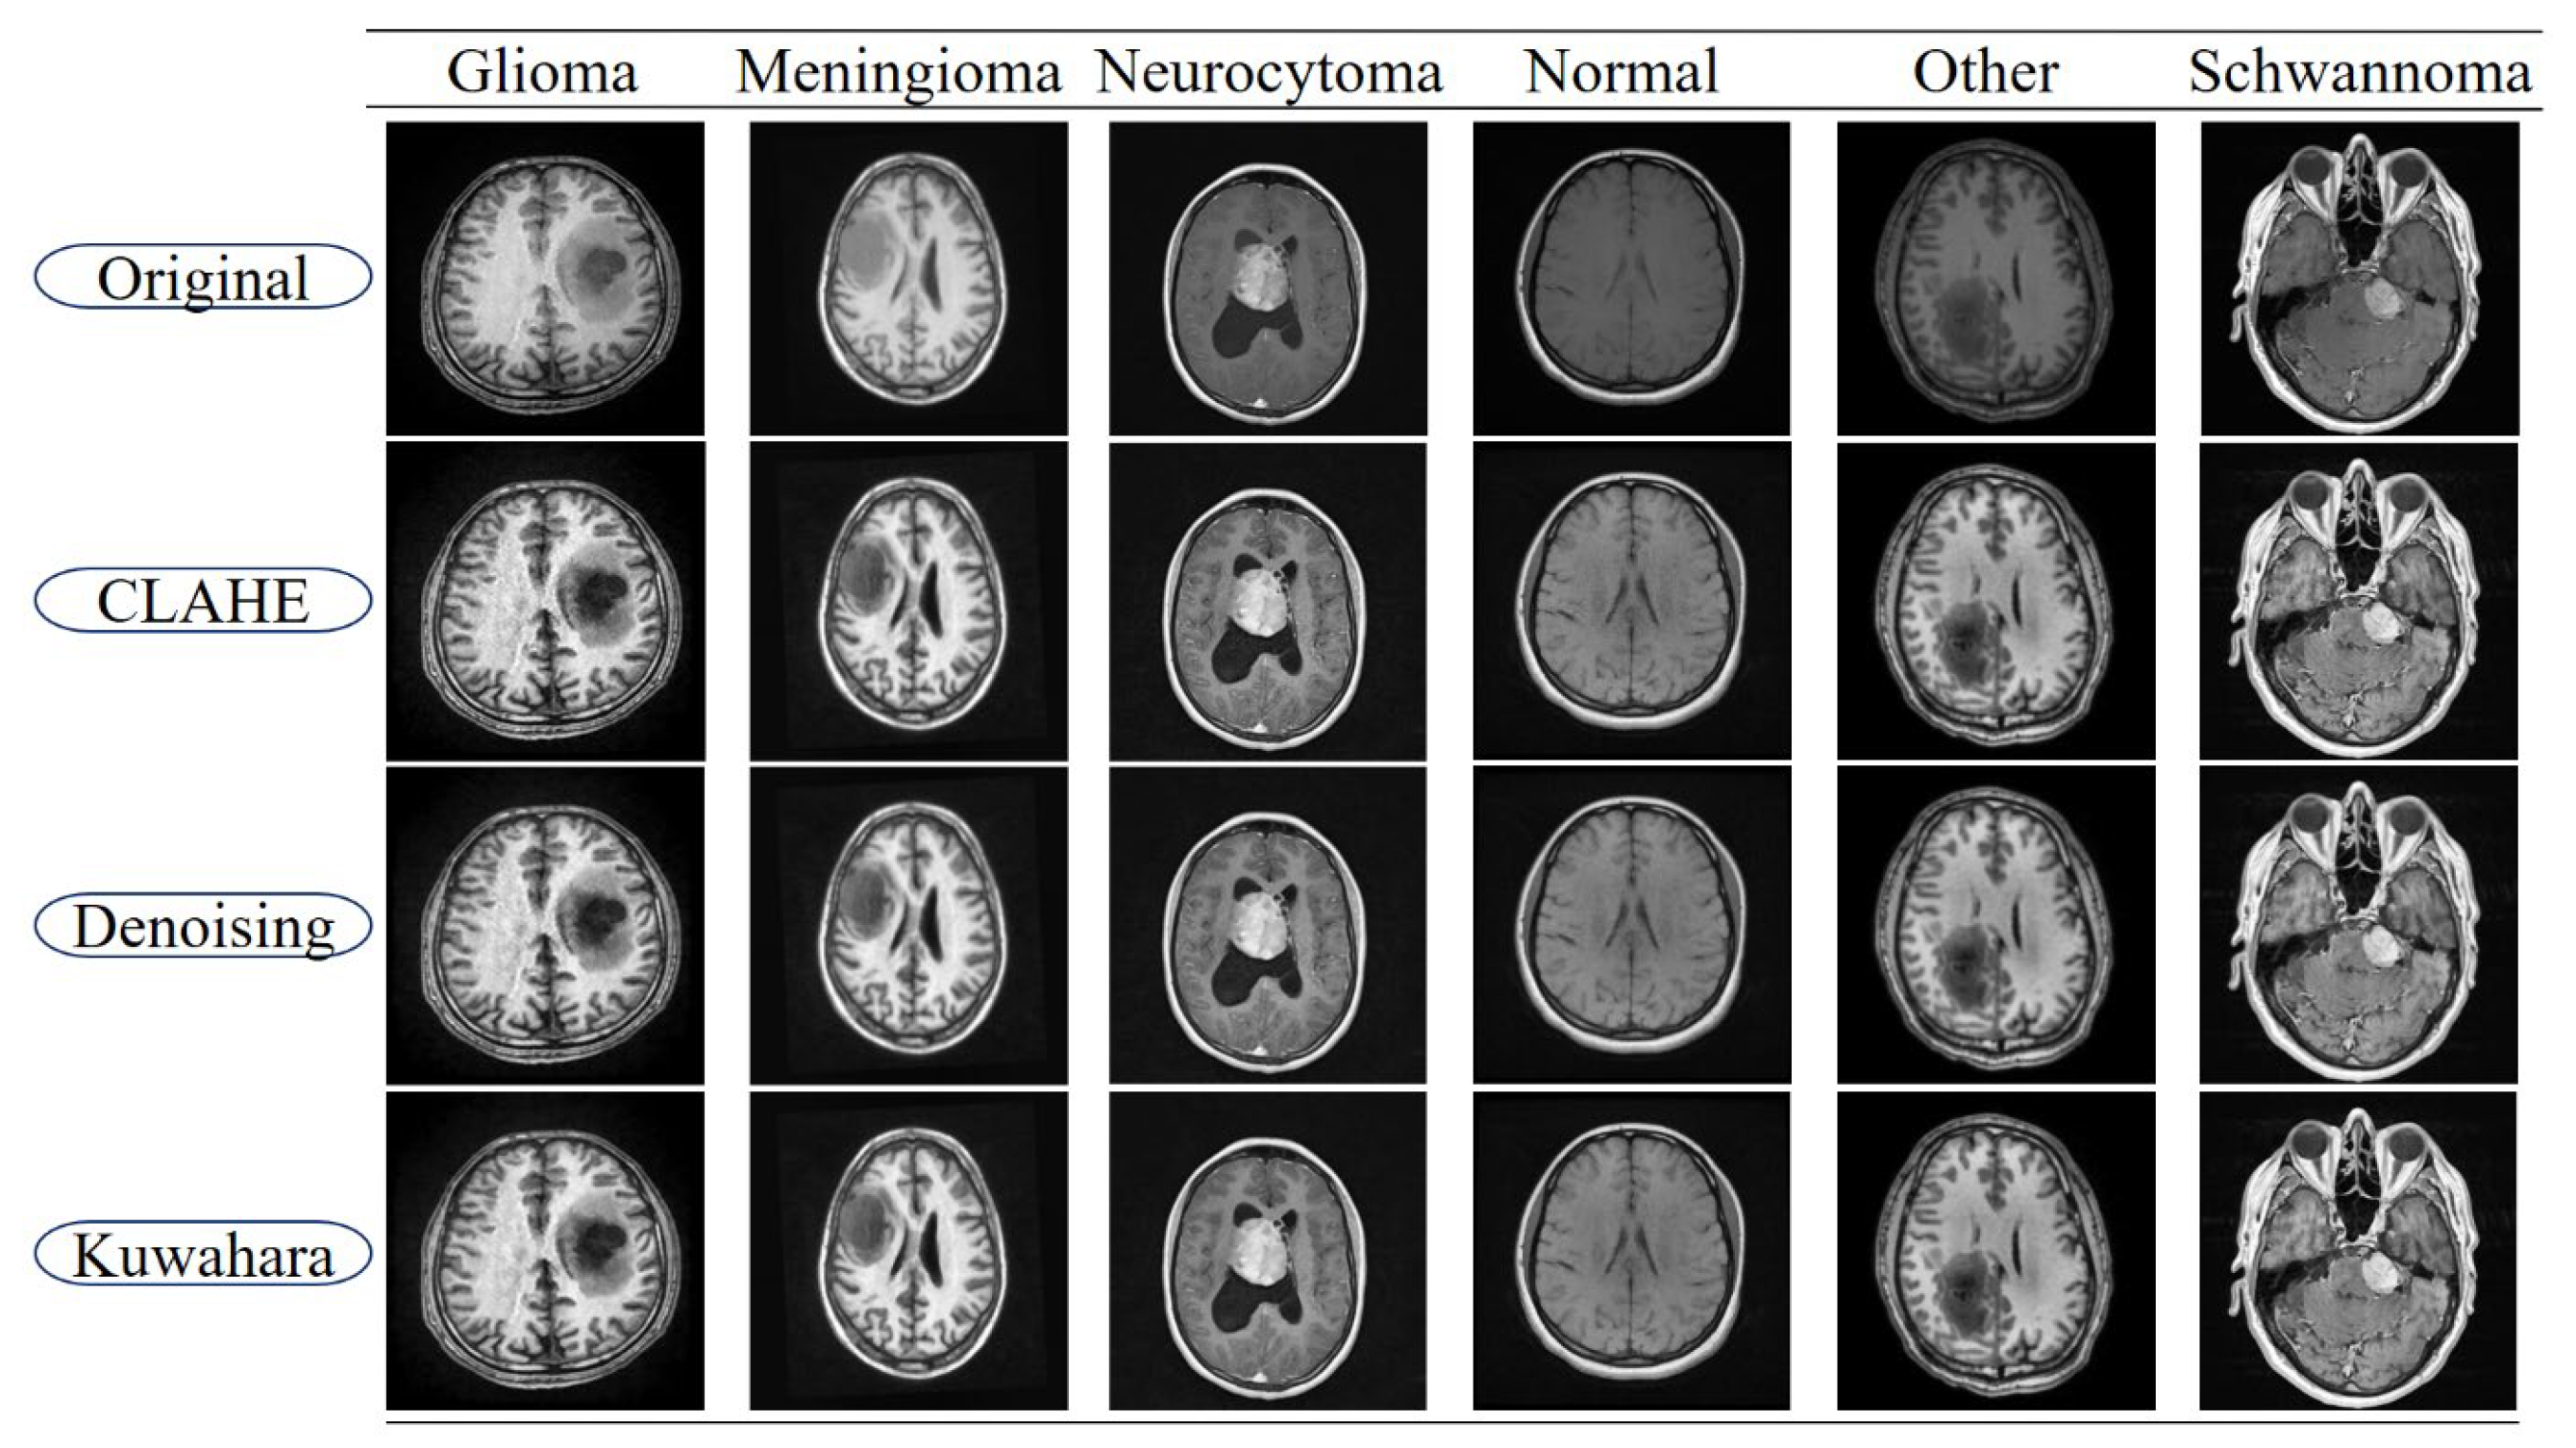

The brain tumor MRI images used in this study were obtained from the BTMRII dataset, shared on the public platform Kaggle [43]. This dataset is an open collection widely referenced in research and comparative experiments. The original BTMRII dataset contains a total of 4448 real MRI images. The images were acquired in the axial plane and include T1, T1-enhanced (T1C+), and T2 modalities with different sequence weights. The original resolution and bit depth of the images may vary within the dataset. Therefore, firstly, all images in the study were rescaled to a uniform network input size of 256 × 256. BTMRII is primarily divided into six classes: Glioma, Meningioma, Neurocytoma, Normal, Other, and Schwannoma. The ‘Normal’ class is divided into two classes: T1 and T2, while the other classes are further divided into three classes: T1, T1C+, and T2, dividing the dataset into a total of 17 different classes. Cataloging is organized with a folder for each class. The set covers a variety of primary brain tumor histologies and some neurological lesion subtypes (example classes: astrocytoma, ependymoma, ganglioglioma, glioblastoma, oligodendroglioma, medulloblastoma, meningioma, pituitary/pituitary adenoma, schwannoma, germinoma, etc.). In this study, the T1, T1C+, and T2 modalities of the six main classes of BTMRII were combined. Thus, 1317 brain MRI images belonging to the Glioma class, 1299 to the Meningioma class, 542 to the Neurocytoma class, 563 to the Normal class, 257 to the Other class, and 470 to the Schwannoma class were used, all in 8-bit and jpeg format. The ground truth annotations were directly obtained from the BTMRII dataset, in which expert radiologists manually delineated the tumor regions on MRI scans. The annotation protocol followed a multi-class segmentation scheme, where each image was labeled with one of the 5 basic predefined tumor categories. For each class, the entire tumor region was annotated as a single mask, rather than subdividing into intra-tumoral components such as necrosis, edema, or enhancing tumor core. Thus, each mask corresponds to a binary segmentation map distinguishing tumor versus non-tumor regions for the respective tumor class. Example images from each of the six classes of the BTMRII dataset are shown in Figure 1.

Figure 1. Sample images from each of the six classes in the BTMRII dataset.